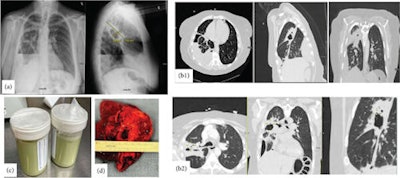

At the hospital, she had a 102° fever, and she was wheezing. A chest x-ray showed a hydropneumothorax, and a computed tomography (CT) chest scan with contrast “revealed a small burden of left-sided acute pulmonary embolism (PE), a large thick-walled irregular cavitary consolidation or mass in the right upper lobe (RUL) with an internal air-fluid level, and a moderate right-sided loculated hydropneumothorax/empyema.” Furthermore, she underwent an ultrasound that showed “bilateral nonocclusive, acute appearing deep venous thrombi (DVT) in the right popliteal, left superficial femoral, and left popliteal veins,” according to the case report.

Figure 1: (a) Initial chest x-ray upon presentation showing extensive heterogeneous right lung opacity, which appears to be a thick-walled cavitary lesion about 4.8 × 10.5 cm. Moderate right loculated hydropneumothorax at the lung base with associated air-fluid level, concerning for empyema. (b) b1: A thick-walled cavitary consolidation or lesion in the posterior right upper lobe. There is a complex moderate right pleural effusion with air-fluid levels, concerning for empyema. There is extensive parabronchial thickening in the right lung. b2: CT chest after chest tube insertion; the yellow marker is pointing to a bronchopulmonary fistula, which was the reason for her continuous air leakage. (c) Frank pus after inserting the chest tube. (d) Right upper lobe abscess after lobectomy.Image and caption courtesy of Zohouri et al. Licensed under CC BY 4.0.

Due to the woman’s severe penicillin allergy, she was given broad-spectrum antibiotics intravenously, as well as heparin for the pulmonary embolism. On her second day at the hospital, a chest tube was inserted and pus was aspirated. Though analysis showed no malignant cells, it showed marked inflammation consistent with empyema. She received intrapleural fibrinolytics and underwent bronchoscopy with bronchoalveolar lavage and biopsy, the authors wrote.

A maxillofacial CT showed no signs of sinusitis or abscesses. On her sixth day in the hospital, the woman underwent a right video-assisted thoracoscopy and thoracotomy, which revealed a large abscess in the right upper lobectomy.